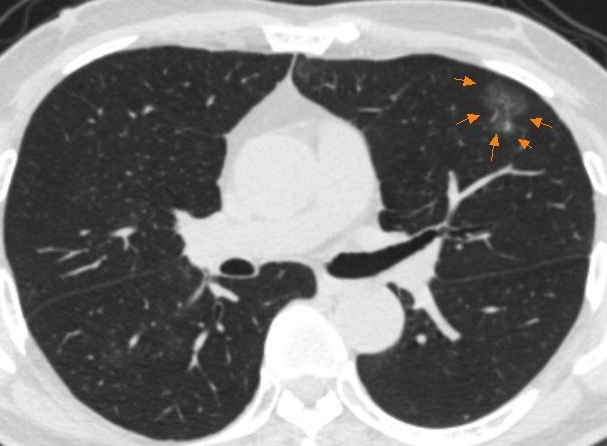

磨玻璃结节见于炎症、出血和肿瘤,与腺癌密切相关,因此有必要对毛玻璃结节进行综合评价并密切随访。

磨玻璃结节的直径和形状与恶性病变的程度密切相关。结节直径越大,有分叶状、毛刺等表现,高度提示为恶性病变。结节直径小,可能是良性的。

磨玻璃结节

对于淋巴结恶性肿瘤可能性高的患者,需要穿刺活检以明确其病理性质。对于无恶性病变趋势的磨玻璃结节,应进行密切随访和复查。在随访期间,结节的密度或直径增加,提示恶性疾病,需要积极活检或直接手术切除。